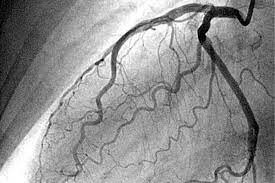

• Angiografía coronaria

Angiografía coronaria

Introducida por Mason Sones. Se realiza por cateterismo cardiaco con ayuda de un medio de contraste (yodo) para visualizar las arterias coronarias y los vasos que alimentan el corazón.